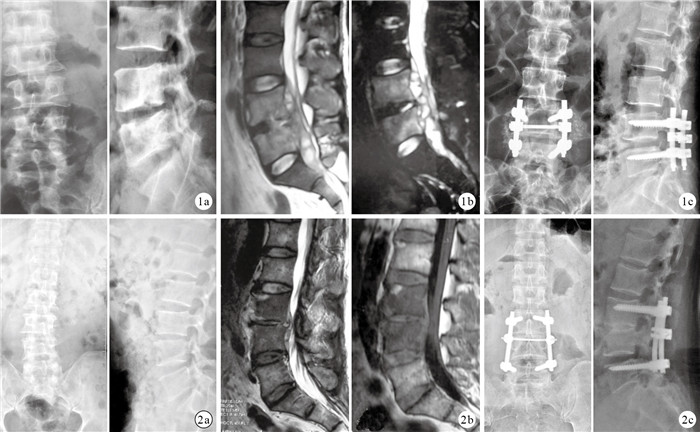

兩組患者術后各時間點VAS評分均較術前明顯下降,差異有統計學意義(P<0.05)。術后同一時間點兩組VAS評分比較,差異均無統計學意義(P>0.05)。見表 1。A組術前有神經功能障礙者46例中,31例神經功能改善明顯;術后3個月ASIA分級為C級1?例,D級14例,E級63例。B組術前有神經功能障礙者42例中,30例神經功能改善明顯;術后3個月ASIA分級為C級1例,D級11例,E級58例。兩組術后ASIA分級比較,差異無統計學意義(Z=0.168,P=0.682)。兩組術后各時間點ESR、Cobb角均較術前明顯降低,差異有統計學意義(P<0.05)。術后同一時間點兩組ESR、Cobb角比較,差異均無統計學意義(P>0.05)。見表 2、3。術后X線片復查示,兩組患者植骨均融合;A組融合時間(8.7±0.3)個月,B組(8.6±0.4)個月,兩組比較差異無統計學意義(t=0.591,P=0.601);末次隨訪時無內固定物松動、斷裂現象出現。見圖 1、2。